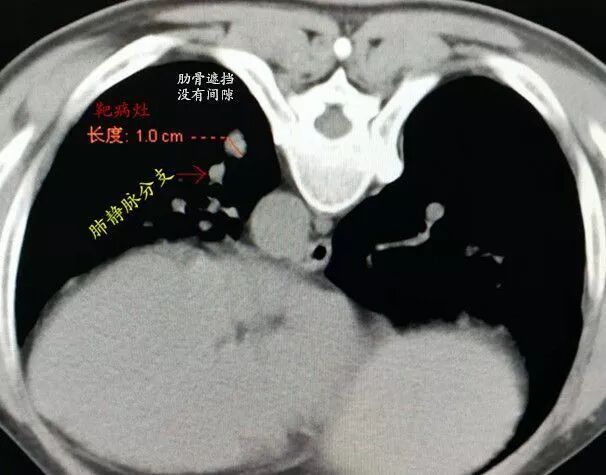

俯臥位時靶病灶空間位置稍有變化,距皮60mm,僅占據一個CT層面,橫徑僅比相鄰的左肺下靜脈略大,且完全被后肋遮擋。

采用頭腳縱軸成角入路沿下位肋間隙斜上方向置入導針,CT顯示導針進入肺內,左右、頭腳方向準確,已達靶病灶邊緣。

沿導針方向順利置入16G活檢槍,CT顯示正中靶心,激發(fā)取材,